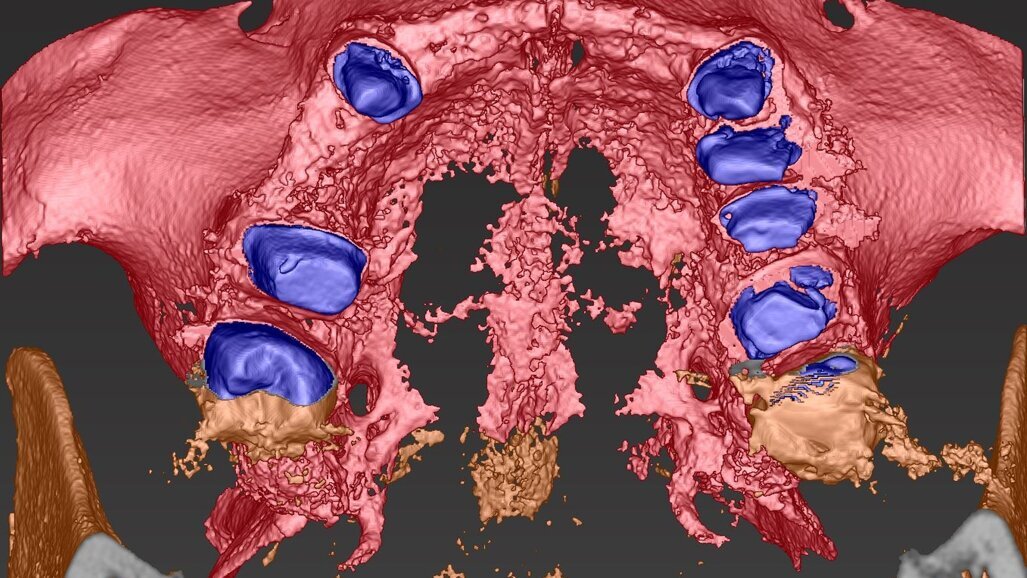

Fig. 8_Impatto visivo della CBCT nella porzione vestibolare che evidenzia la marcata lacuna ossea che impatta sull’estetica del II° sestante.

Fig. 9_Nel taglio sagittale è possibile verificare la porzione ossea presente sull’intera arcata, si notano le preparazioni degli elementi naturali che faranno da link per la connessione nel progetto elaborato.

Fig. 14_Visione palatale del wax-up completo in marrone, sovrapposto alla visione ossea in azzurro con gli elementi sottostanti in viola. L’impianto in posizione 1.5 anche se progettato non è stato inserito preferendo un progetto protesico convenzionale con il collegamento a ponte degli elementi limitrofi.